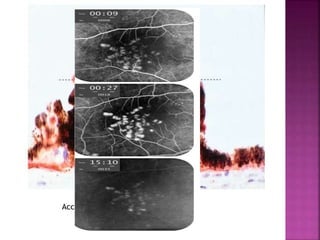

 Due to breakdown of outer blood retinal

A . In subretinal space

As in CSR

Early hyperfluorescence

Increase in size and intensity

B . In sub RPE space

As in PED

Increase in intensity but

not in size